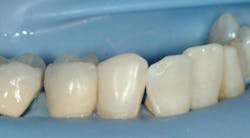

The following images show a patient with limited finances but a strong desire to retain her teeth. The crowns present in the quadrant placed by a previous dentist show that the patient at one time had adequate finances for crowns.

The technique for building up restorations to restore deep carious lesions follows: